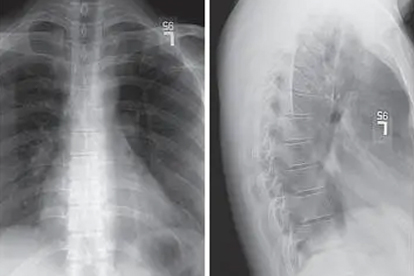

锻炼需在康复治疗师指导下进行,避免过度扭转或负重动作。建议结合定期影像学评估,侧弯角度超过20度需配合矫形支具。日常注意双肩背包交替背负,睡硬板床并采用仰卧位。青少年患者应保证每日1小时中高强度运动,补充维生素D和钙质促进骨骼发育。